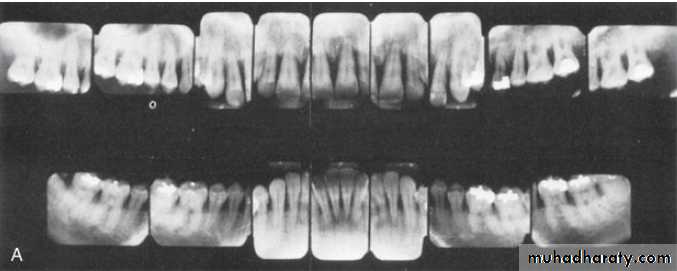

Radiographic examination must be individualized, depending on the initial severity of the case and the findings during the recall visit. These are compared with findings on previous radiographs to check the bone height and look for repair of osseous defects, signs of trauma from occlusion, periapical pathologic changes, and caries.